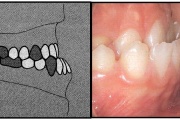

kahepoolse lõhega lapse hambumus

Valehambumus

Hammaste asendianomaaliad on tingitud tavaliselt arenguhäirest.